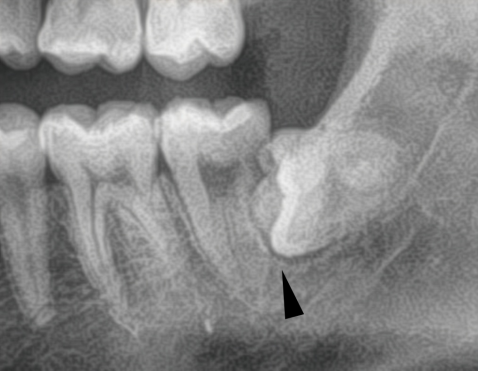

8.手前の歯の根を押す場合、押された歯の根は溶けてしまいます

一番左の親知らずが、大事な隣の歯の根を溶かしてしまいました。

下の親知らずが、前の歯の根を溶かしてしまいました。